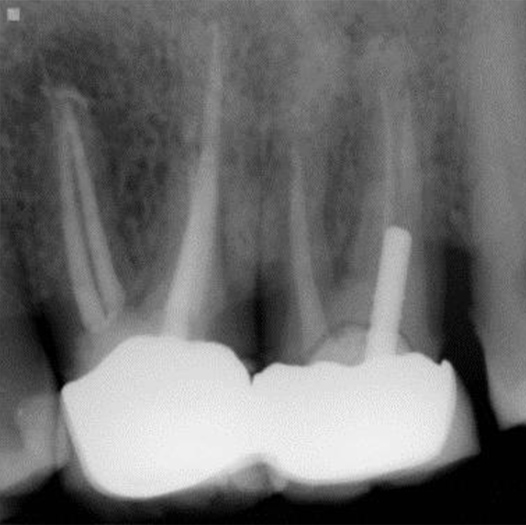

After

After Root Canal treatment